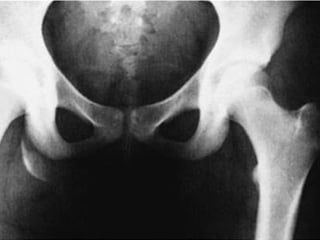

Tile B1 / Young APC II